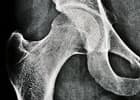

Knochen liegt in zwei verschiedenen Strukturen vor. Der kompakte Knochen, die „Compakta“, bildet die harte Röhre z.B. des Oberschenkel-Knochens. Der netzartige Knochen, die „Spongiosa“, liegt im Inneren der Kompakta, und zwar im Bereich der Knochenteile, welche die Gelenke bilden, und in den Wirbelkörpern.

Spongiosa

Die Spongiosa stützt die Gelenkflächen ab und überträgt die auftretenden Kräfte auf die Kompakta. Die geometrische Anordnung der Spongiosa folgt den Kraftlinien, die durch ein Gelenk wirken. Diese Kraftlinien werden Trajektorien genannt. Die gesamte Knochenmasse besteht etwa zu 80% aus Kompakta und zu 20% aus Spongiosa.